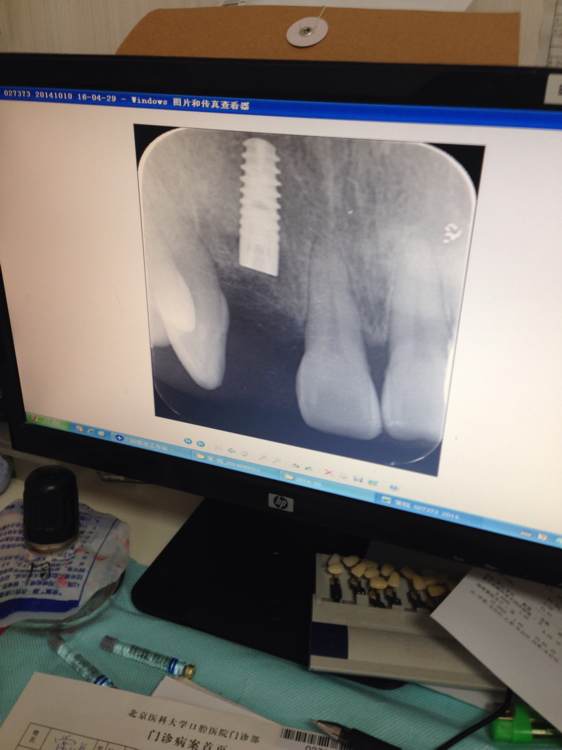

做完后拍的片,感觉钉冒整个被缝合在里边了,为什么有的吧友刚做完的钉冒露在外边呢?有没有专家给解释下为什么谢谢!

这样可以减少感染的机会,6个月以后要做二期手术。直接暴露的,可能不用植骨。